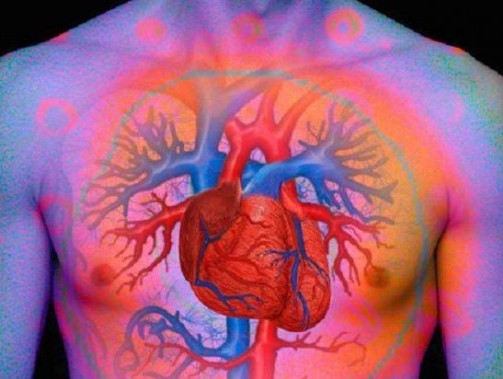

WASHINGTON – L’ansia può uccidere. Se si soffre di malattie cardiache è bene ricordarlo: stress e agitazione aumentano il rischio di morte prematura. L’allarme è stato lanciato dal Duke University Medical Center, che ha sottolineato come negli ultimi anni le sindromi ansiose siano in netto aumento, con conseguente impennata nel consumo di psicofarmaci e ansiolitici.

L’ansia, però, non riguarda solo la salute psichica, ma anche quella fisica e generale. Gli stati ansiosi raddoppiano il rischio di morte per tutte le cause nei pazienti con malattie cardiache. Se poi il paziente soffre anche di depressione il rischio si triplica.

I ricercatori del Duke University Medical Center raccomandano a tutte le persone che soffrono di patologie cardiache di sottoporsi a screening per individuare depressione o ansia, due patologie spesso correlate: l’ansia aumenta l’attività del sistema nervoso simpatico che controlla la pressione sanguigna, con conseguenze sull’umore e, soprattutto, sulla salute del cuore.